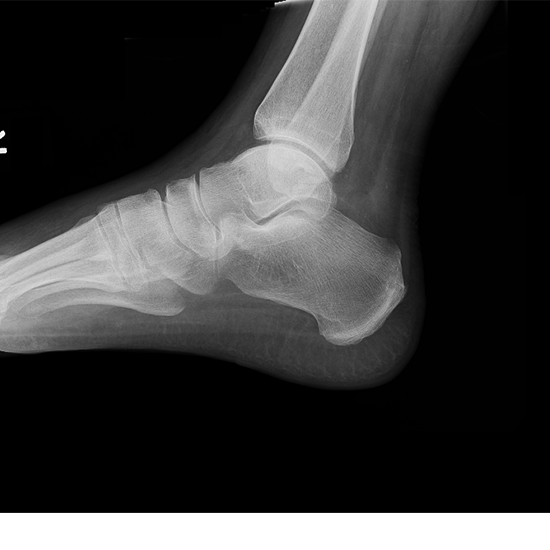

If you have significant heel pain, your doctor may perform a Calcaneus X-ray to determine the reason. The lateral view of the calcaneus is part of the two-view calcaneus series. It is used to evaluate the talocalcaneal, talonavicular, talocrural, and calcaneus joints. During the scanning technique, a radiation beam is transmitted through the heel, and all available pictures are shown on the screen.